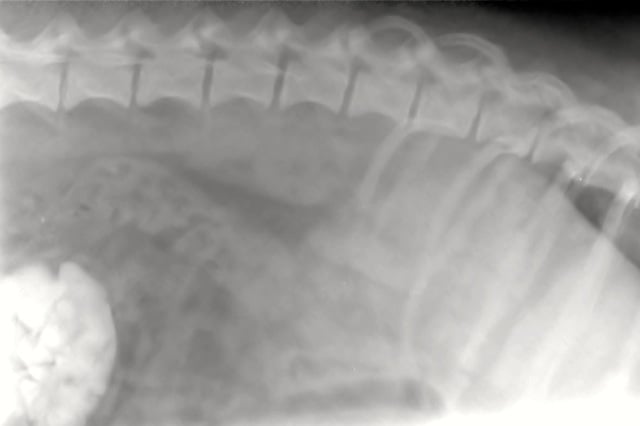

Once we had her anaesthetised we could feel some scrunching in the her bladder. We took an xray and this is what we saw:

That bright white area on the lower left corner of the image is Lilly’s bladder and it is full of stones.